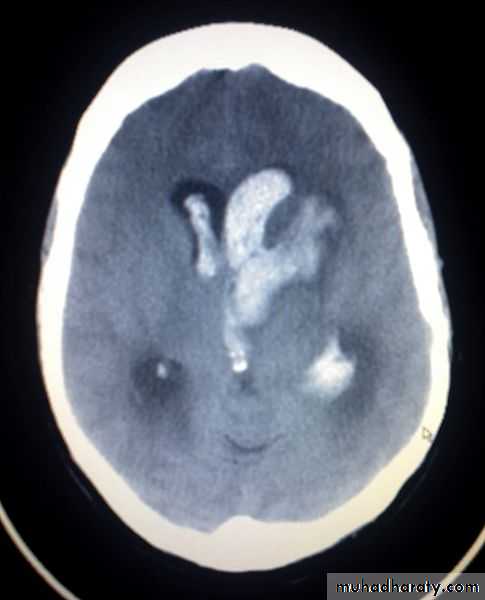

Intra ventricular IVH

Acute Intra cerebral hematoma

CT finding :Hyper dense area , surrounded by edema , any where within the brain parenchyma.

Shifting of the midline

Compression of the ipsi lateral ventricle .